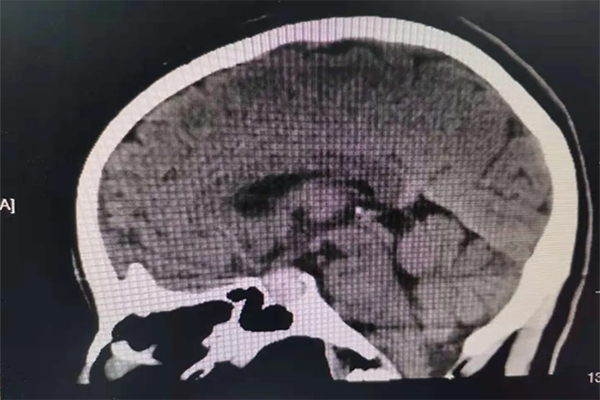

患者段女士,42歲。反復頭暈、眼花、心慌已經5月多了,5月前當地醫院頭顱CT未見明顯異常。1周前患者頭暈、眼花越發嚴重,輾轉多個醫院無果后,患者來到我院內科住院檢查,完善頭顱CT后,發現鞍區占位,考慮垂體腺瘤可能。

當外一科楊金雷主任到達內科時,已經找不到段女士的身影了。楊主任通過查看患者病歷,電腦閱讀CT,診斷患者為垂體腺瘤并出血可能,即患者可能存在瘤卒中。要求立刻打電話讓患者返回醫院接受正規系統的治療。

5個月的時間,CT結果提示鞍區占位病變,進行性增大,考慮瘤卒中可能。